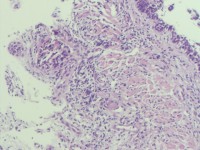

咔血3月,纤维支气管镜:右侧肺下叶基底段黏膜增生。能诊断肺部鳞状细胞癌吗?